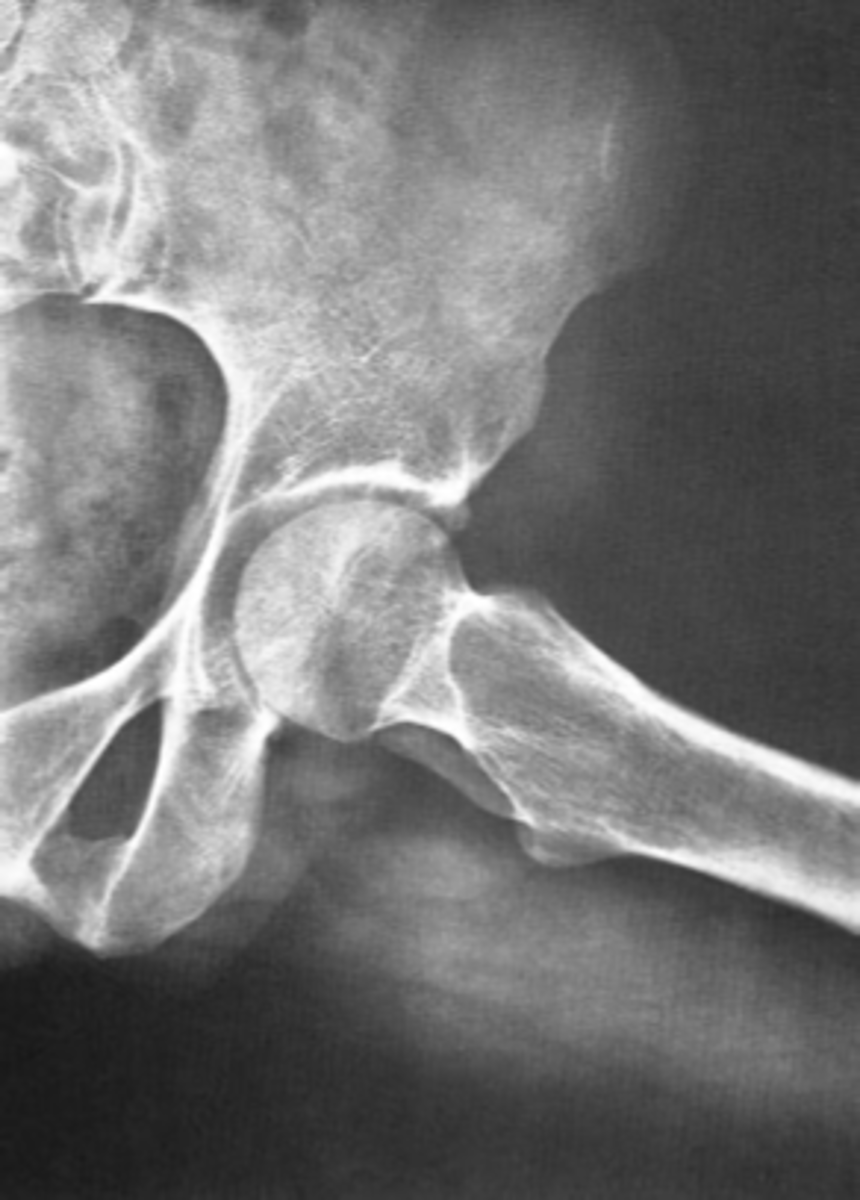

Frog-leg (lateral) hip

ID standard unilateral hip projection

<p>ID standard unilateral hip projection</p>

13